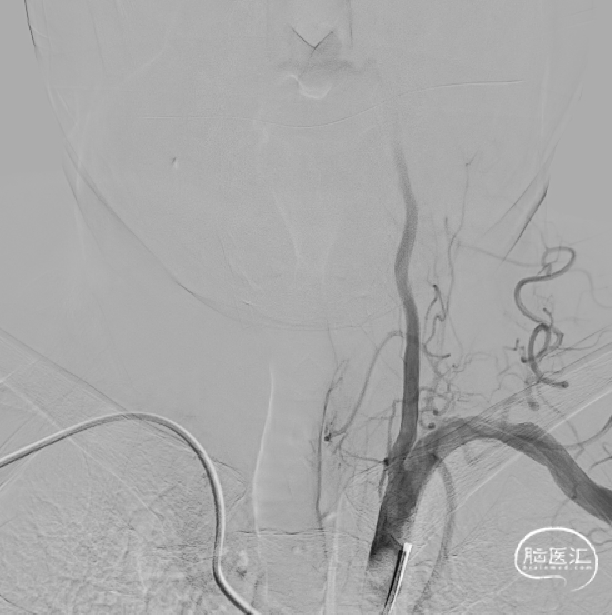

DSA:右侧椎动脉V4重度狭窄

术中:赛诺神畅颅内药物洗脱支架NOVA DES®2.5*12mm到达狭窄段

术中:赛诺神畅颅内药物洗脱支架NOVA DES®缓慢充盈(8atm)